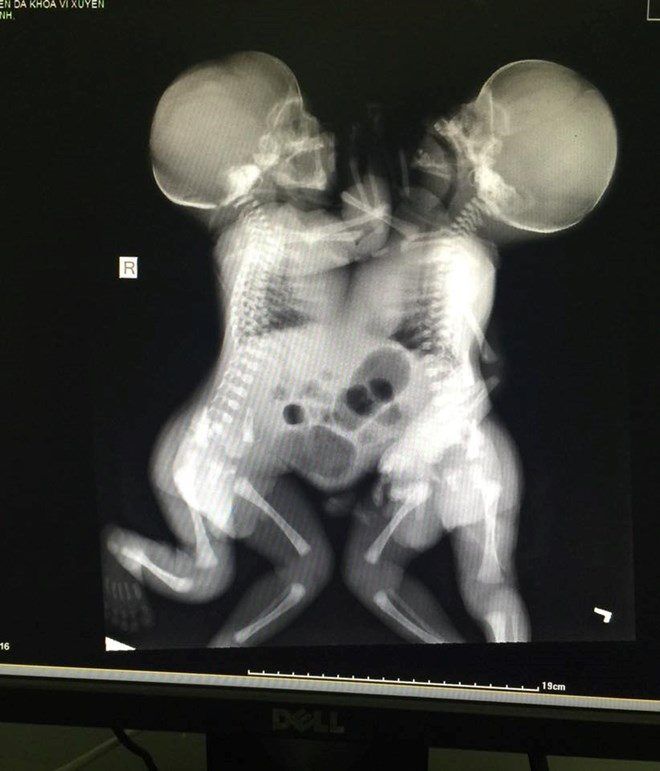

Hình ảnh hai bé bị dính một phần cơ thể.

Lúc ấy các bác sĩ chỉ biết là thai đôi chứ không biết là hai thai dính nhau. Trong quá trình mổ sinh, bác sĩ phát hiện 2 bé trai dính liền với nhau từ ngực đến bụng, chung dây rốn, 2 thai có trọng lượng 4900gr.